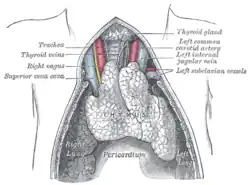

The thymus gland cells form part of the body's immune system. In those with myasthenia gravis, the thymus gland is large and abnormal. It sometimes contains clusters of immune cells which indicate lymphoid hyperplasia, and the thymus gland may give wrong instructions to immune cells.[24]

A juvenile thymus shrinks with age.

A juvenile thymus shrinks with age. -

Myasthenia gravis (MG) is a long-term neuromuscular disease that leads to varying degrees of skeletal muscle weakness.[1] The most commonly affected muscles are those of the eyes, face, and swallowing.[1] It can result in double vision, drooping eyelids, trouble talking, and trouble walking.[1] Onset can be sudden.[1] Those affected often have a large thymus or develop a thymoma.[1]

Myasthenia gravis is generally treated with medications known as acetylcholinesterase inhibitors such as neostigmine and pyridostigmine.[1] Immunosuppressants, such as prednisone or azathioprine, may also be used.[1] The surgical removal of the thymus may improve symptoms in certain cases.[1] Plasmapheresis and high dose intravenous immunoglobulin may be used during sudden flares of the condition.[1] If the breathing muscles become significantly weak, mechanical ventilation may be required.[1] Once intubated acetylcholinesterase inhibitors may be temporarily held to reduce airway secretions.[8]

Surgery

As thymomas are seen in 10% of all people with the MG, people are often given a chest X-ray and CT scan to evaluate their need for surgical removal of their thymus and any cancerous tissue that may be present.[18][37] Even if surgery is performed to remove a thymoma, it generally does not lead to the remission of MG.[49] Surgery in the case of MG involves the removal of the thymus, although in 2013 there was no clear indication of any benefit except in the presence of a thymoma.[53] A 2016 randomized controlled trial, however, found some benefits.[54]